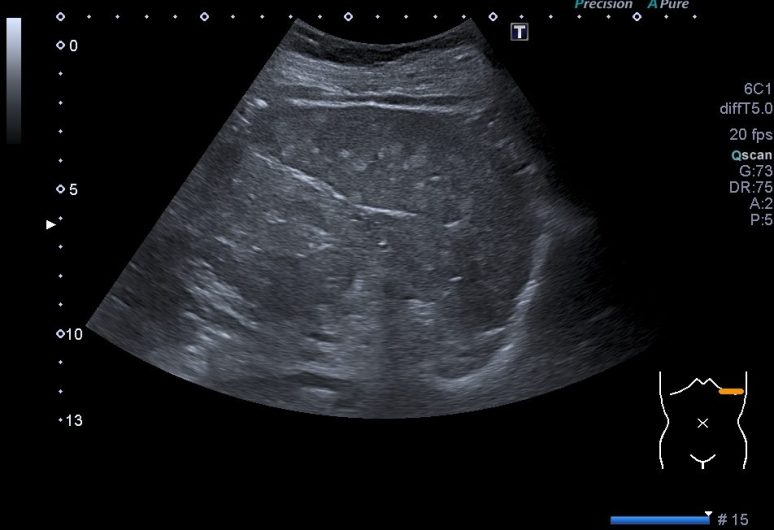

Estas dos imágenes superiores son la normalidad. Corte axial y longitudinal del Bazo. Homogéneo, sin lesiones, grande sin llegar a la esplenomegalia. Bazo de libro.